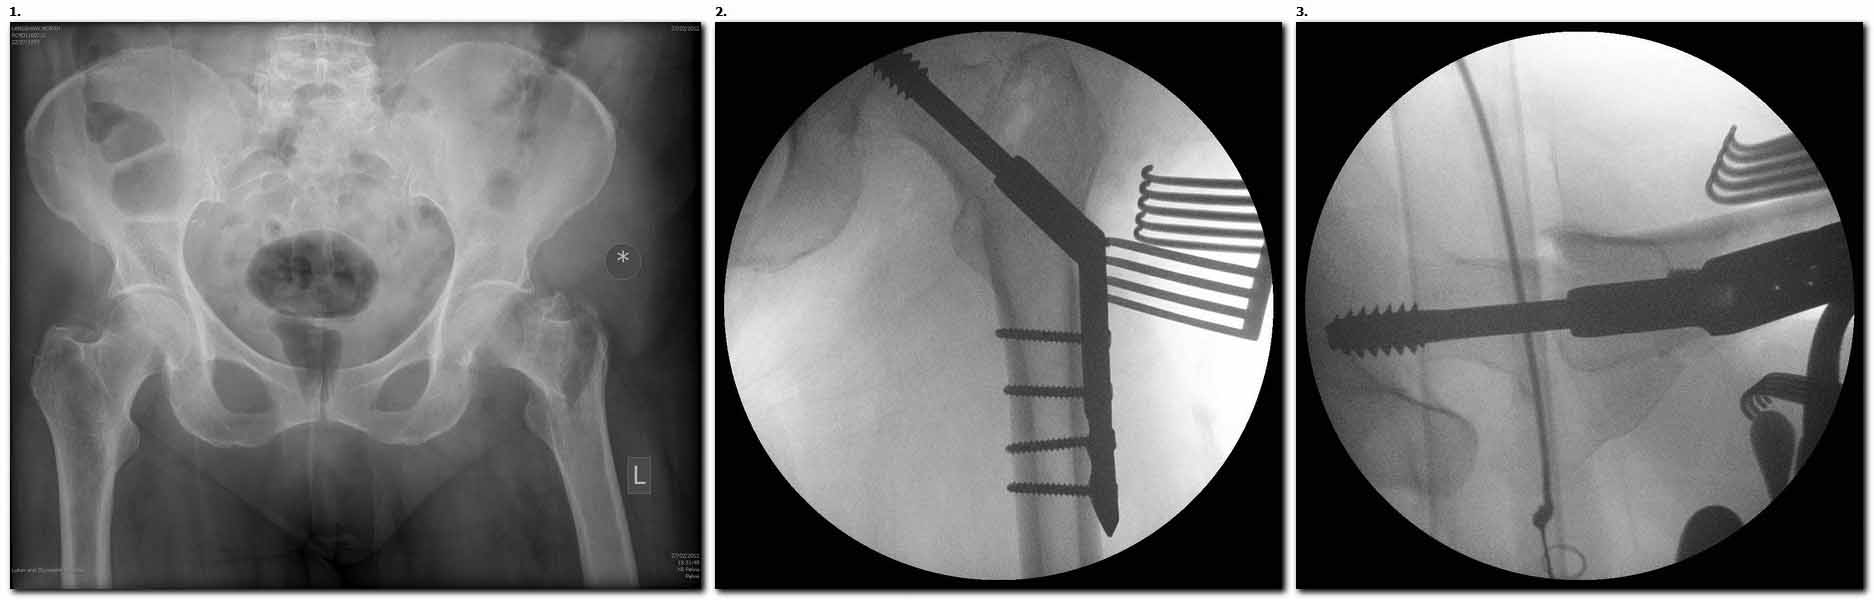

> Банальный рутинный перелом чрезвертельной зоны лечимый DHS. Первая

> операция, которую

> должен как-бы выучить начинающий ортопед. Не боится грубостей, мата и

> молотка, но может

> стать грозным оружием в борьбе за смерть пациента. Пример DHS фиксации

> перелома. Какой режим

> предложите, коллеги? Стараемся более нежно мобилизовать больного? Или

> агрессивно?

> Принимаются замечания, одобрения и пожелания.